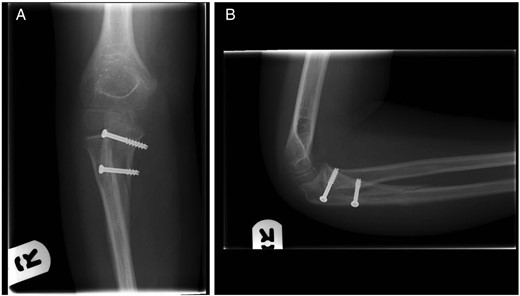

Under general anaesthesia, the fracture was clearly visualized using a medial approach to the proximal ulna, splitting the flexor muscle mass longitudinally. Minimal dissection was required distally secondary to a traumatic defect in flexor carpi ulnaris. The ulnar nerve was identified and protected throughout. Following reduction the fracture was fixed securely using 2 × 4.0 mm partially threaded cannulated screws; the guide wires were passed in an anterior to posterior direction and the screws were inserted from posterior to anterior through two separate stab incisions on the subcutaneous ulnar border for ease of removal in the future. The elbow was taken through a full range of motion and satisfactory fluoroscopic images were obtained (Fig. 3). A posterior long arm back slab was applied and completed the following day prior to discharge.

(A) Anterior–posterior and (B) lateral fluoroscopy images with two cannulated screws in situ. Fluoroscopy images taken in theatre post-fracture fixation.